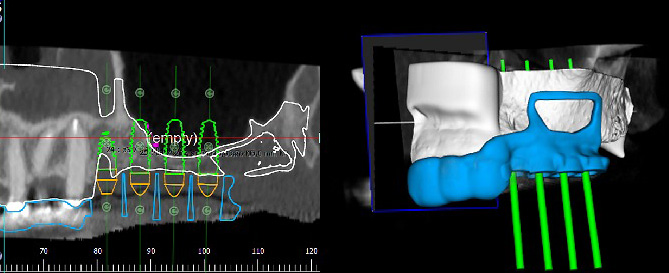

К сожалению, по нашим данным (Аванесов, Седов, Морданов и др, 2018) встречаемость признаков данной артерии на КЛКТ составляет 76%. При условии визуализации ААА на КЛКТ, после виртуального планирования расположения имплантатов, возможно спроектировать дизайн хирургического шаблона таким образом, чтобы можно было безопасно провести технику открытого синус-лифтинга (рис 2).

Рисунок 2. Планирование положения имплантатов на КЛКТ.

Спроектирован дизайн шаблона, который также включает рамку для антротомии, разработанную в соответствии с протоколом операции.